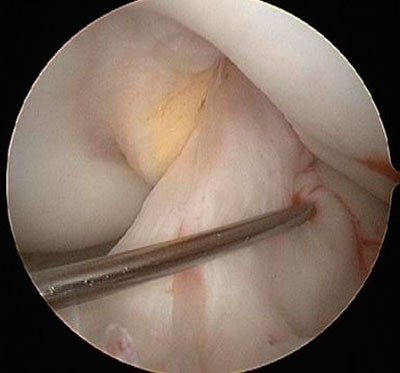

При проведении операции, специалист заполняет данную капсулу особым физиологическим веществом до определенной степени растяжения и, затем, вводит в пространство сустава артроскопическое оборудование, позволяющее детально увидеть все элементы колена, включая особо труднодоступные участки.

Вначале специалист выполняет в районе колена 2 прокола (порталы) и размещает там необходимый инструментарий и и артроскоп.

Тщательно продуманное и выверенное местоположение таких порталов исключает вероятность повреждения сосудов и нервных волокон. Далее, посредством специального медицинского насоса, в сустав запускается физраствор, позволяющий удалить поврежденные элементы и обеспечить наилучшую видимость суставных структур.

Артроскоп, представляющий собой оснащенную изнутри линзами четырехмиллиметровую стальную трубку длиной 20 см, подключается к световоду ксенонового типа и камере, посредством которых на монитор выводится достаточно качественное изображение.

В процессе операции хирургом применяются различные виды инструментария, действия которых контролируются именно артроскопическим прибором.